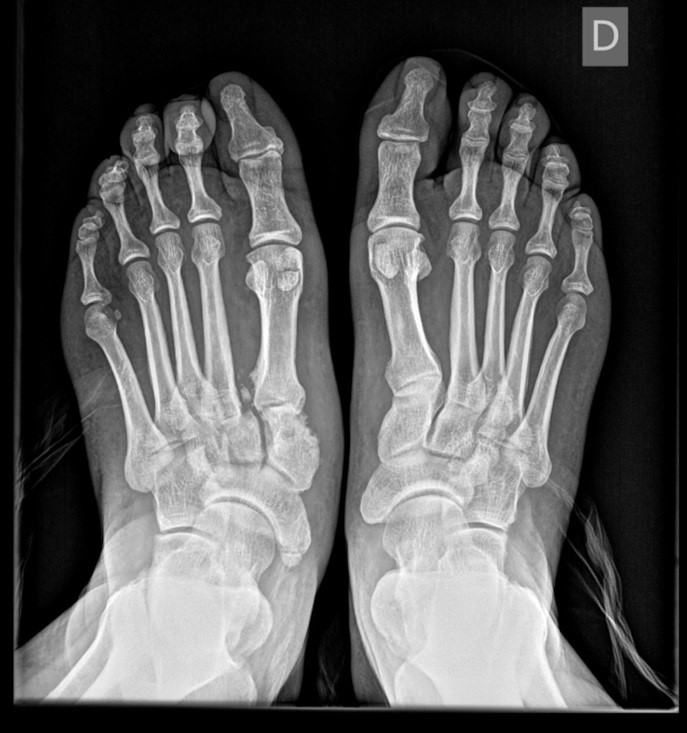

La prueba de elección sería la radiografía ya que nos permite ver las lesiones en hueso, a dosis bajas de radiación, en comparación con otras pruebas más específicas como el TC. Recordar que hablamos en todo momento de lesiones en el pie, donde las más frecuentes son las de tipo óseo.

El estudio que se utiliza con más frecuencia es la radiografía simple: pie en proyección anteroposterior y lateral con apoyo.